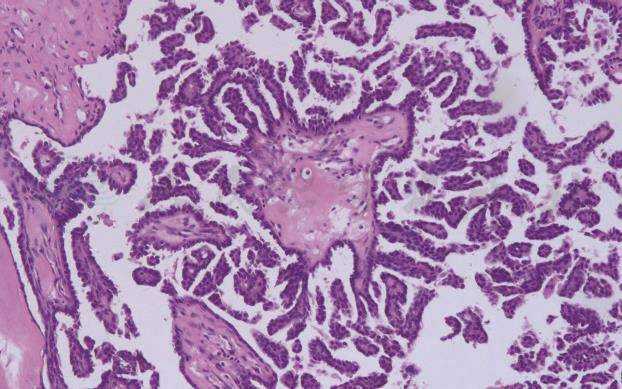

图2微乳头亚型浆液性交界性囊腺瘤(×10)

微乳头亚型SBT形态特点是囊壁或粗短乳头表面直接延伸的纤细、无间质的细胞微乳头结构或筛状结构,乳头的长度至少为宽度的5倍,有的区域细胞几乎呈实性或巢状分布,细胞核一致、有小核仁(图2),具有以上生长方式的病变最大径 ≥ 5mm时方可诊断。